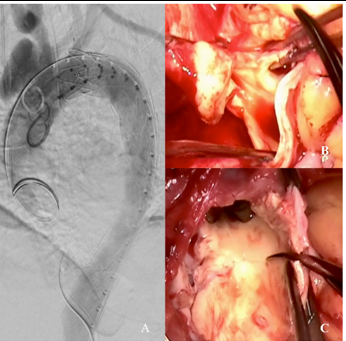

Figure 2. A. Completion aortogram after initial endovascular repair of the descending thoracic aorta. B. Intraoperative image demonstrating the whitish, inflamed and thickened ascending aorta. C. Intraoperative image demonstrating intimal thickening and multiple penetrating defects in the inner curvature of the open aortic arch.